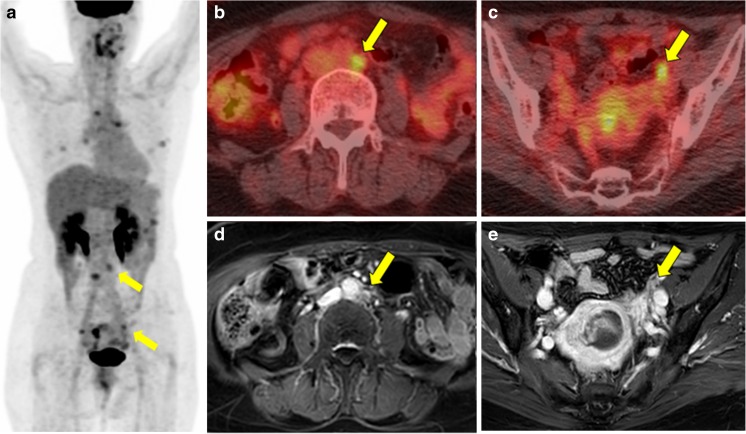

Two patients had false negative results and 4 had false positive results on FDG PET/CT. There was a significant difference in sensitivity between FDG PET/CT and MRI (p = 0.014). The median SUVmax of 12 positive findings of para-aortic LN was 8.42 (range: 2.10–17.58), and the median TLR was 4.40 (range 0.83–6.89). In six cases for para-aortic LN metastasis with positive findings on FDG PET/CT and negative findings on MRI, the pathologic results were positive. In these cases, while the median size of metastatic LNs was 7.05 mm (range 3.70–8.40 mm), the median SUVmax of metastatic LNs was 8.18 (range 2.10–15.97). Figure 1 reflects a representative case of a patient with matched positive findings, whereas Fig. 2 shows a discrepant case between FDG PET/CT and MRI for detecting pelvic and para-aortic LN metastasis.

Fig. 1.

Case of a 55-year-old woman with uterine carcinosarcoma who underwent FDG PET/CT and MRI. a MIP image shows focal intense FDG uptake in the endometrium (SUVmax: 10.89, TLR: 6.94), para-aortic LNs (SUVmax: 6.91, TLR: 4.40), right external iliac (SUVmax: 6.29 and TLR: 4.01), and perigastric LNs, and Rt. subhepatic nodule. b Fusion images of FDG PET/CT for para-aortic LN and c pelvic LN, d enhanced MRI of heterogeneous endometrial mass with large-sized para-aortic (14 mm), and e right external iliac LNs (11 mm) which suggest uterine malignancy with pelvic and para-aortic LN metastasis. After surgery, uterine carcinosarcoma with para-aortic, right external iliac LN metastasis, and peritoneal seeding metastasis was confirmed. Yellow arrows indicate para-aortic and pelvic LN metastasis

Fig. 2.

Case of a 58-year-old woman with uterine carcinosarcoma who underwent FDG PET/CT and MRI. a MIP image shows focal intense FDG uptake in the endometrium (SUVmax: 10.90, TLR: 3.81), para-aortic LNs (SUVmax: 4.86, TLR: 1.70), and both external iliac LNs (SUVmax: 4.97 and TLR: 1.74 for Rt; SUVmax: 4.12 and TLR: 1.44 for Lt.). b Fusion images of FDG PET/CT for para-aortic LN and c pelvic LN suggest LN metastasis. d Enhanced MRI: heterogeneous endometrial mass with small-sized (less than 1 cm) para-aortic and e left external iliac LNs suggest uterine malignancy without LN metastasis. After surgery, uterine carcinosarcoma with para-aortic and both external iliac LN metastasis was confirmed. Yellow arrows indicate para-aortic and pelvic LN metastasis